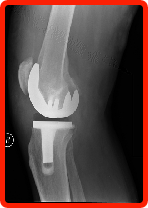

Total Joint Replacement replaces your diseased joint and eliminates the damaged bearing surfaces causing the pain. The implants offer renewed stability, eliminating pain, and providing improved motion with minimum wear and tear. This provides pain-free mobility with a much higher quality of life for the patient. These replacements are most common with knees, hips, and shoulders.

In knees, for example, there are other alternatives available. The Unicompartmental Partial Knee Replacement involves putting an implant on just one side of the knee. Again, like in joint resurfacing, the doctor is able to eliminate the diseased portion of the knee and leave the healthy portion. By retaining undamaged parts of the knee, the joint may bend better and function more naturally.